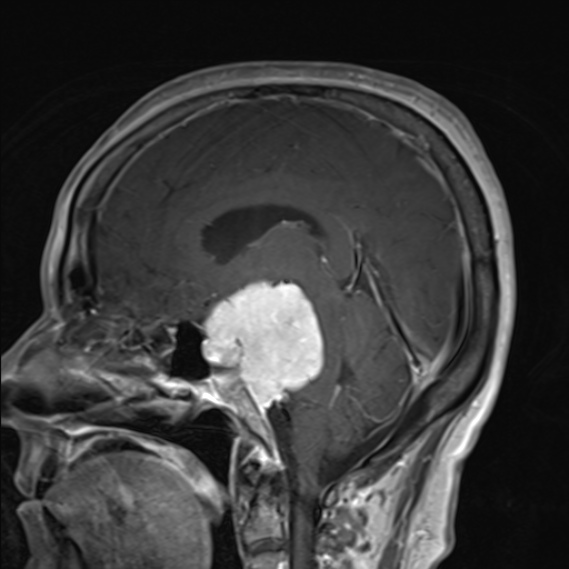

• 腦膜瘤的典型CT表現(xiàn)是什么?腦膜瘤MRI表現(xiàn)有哪些?

腦膜瘤的典型CT表現(xiàn)是什么?腦膜瘤MRI表現(xiàn)有哪些?

2021-08-04 10:48:50

腦膜瘤生長(zhǎng)緩慢,常壓迫周圍組織引起相應(yīng)的神經(jīng)癥狀和體征,造成不同的障礙與腫瘤部位有關(guān)。腦膜瘤的典型CT表現(xiàn)是什么?腦膜瘤MRI表現(xiàn)有哪些?...